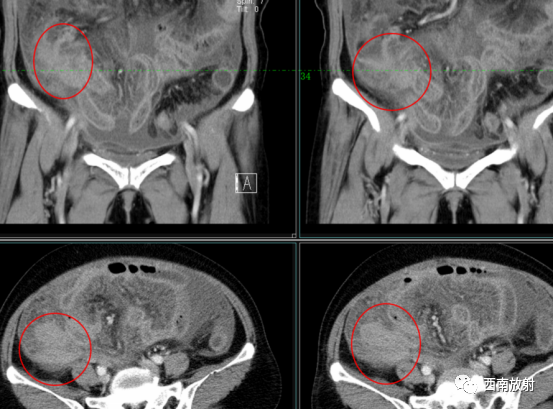

病例

女,70岁。

主 诉 :腹胀、血尿、血便3天

现病史:于2021年06月03日无明显诱因下出现腹胀、血尿、血便,伴纳差、乏力、上腹部胀痛,为终末血尿,肛门擦拭物沾血,为少量血丝,无头晕、眼花、头痛、恶心、呕吐、下肢水肿、眼睑水肿,无心悸、气促、关节疼痛、畏寒、发热、咯血、盗汗、胸痛、少尿等,病后在当地诊所服用口服药物,具体不详,症状未见改善,今日为进一步诊治来我院门诊就诊,门诊经询问病史、查体及查血常规、尿常规等检查,拟”腹腔积液查因”收入我科住院。病后精神、睡眠、食欲尚可,体重无明显变化。

MRI及CT增强扫描:阑尾区域见团块状影,周围脂肪间隙模糊,增强扫描渐进性强化。

最终病理:阑尾神经内分泌瘤。